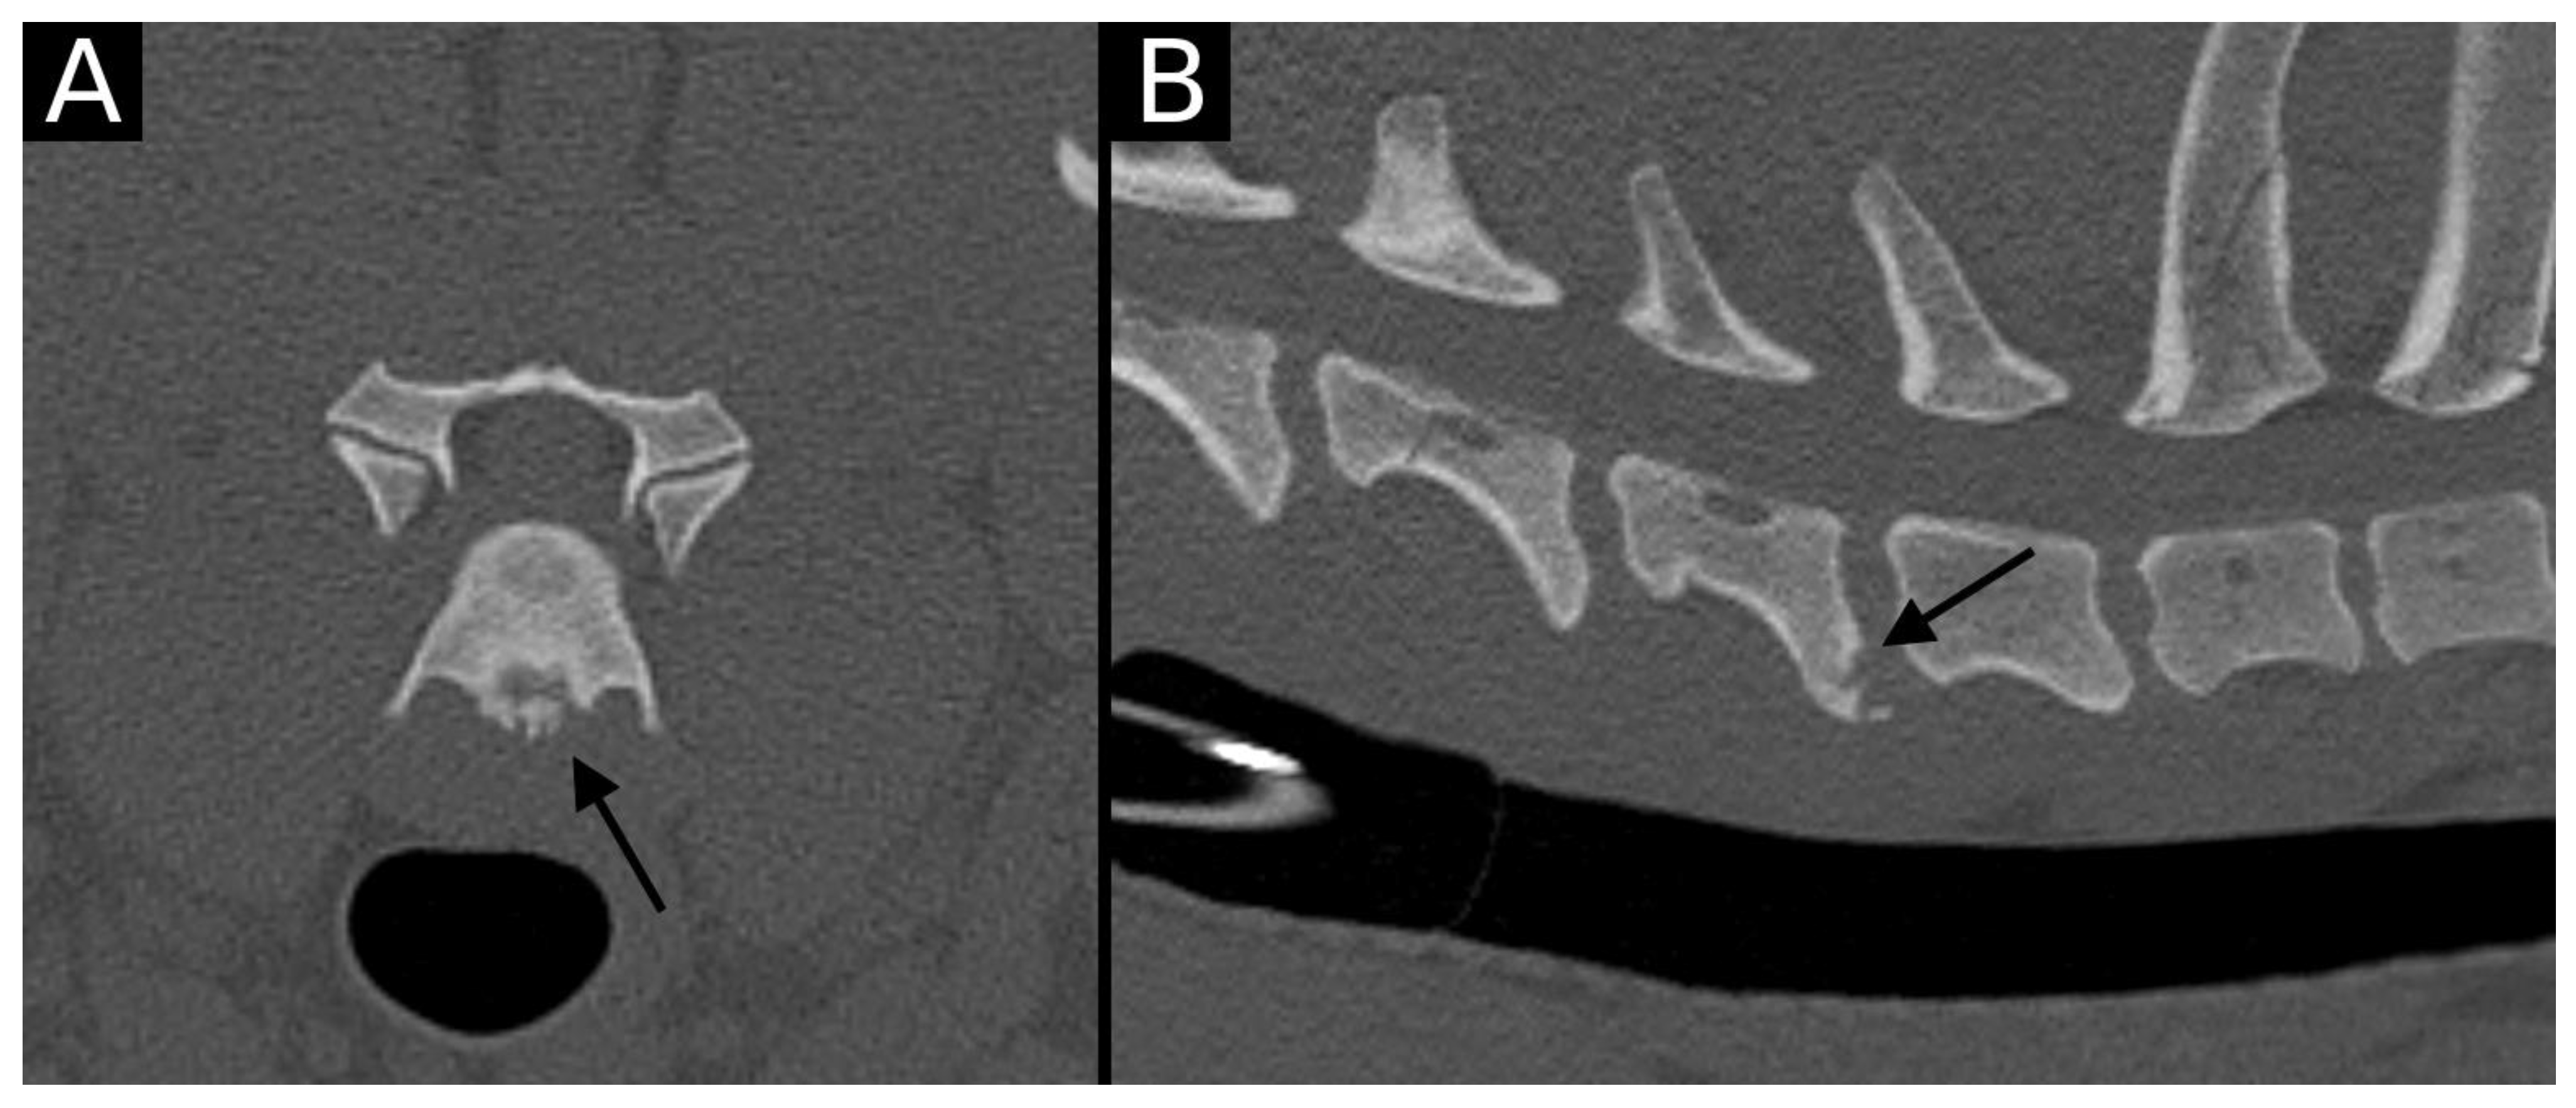

Figure 7. Transverse (A) and sagittal (B) reconstructions in the bone algorithm in the only dog with an intervertebral disc herniation. The C6–C7 intervertebral space is markedly narrowed, with the presence of moderate to marked spondylosis deformans, mild endplate sclerosis and mineralized herniated disc material. An irregularly defined contour defect is observed at the dorsal aspect of the caudal endplate of C6 (arrow). This was classified as EPJA Type A. The adjacent intervertebral disc spaces are also narrowed, with endplate sclerosis and spondylosis deformans. The vacuum phenomenon is also observed at C7–T1.